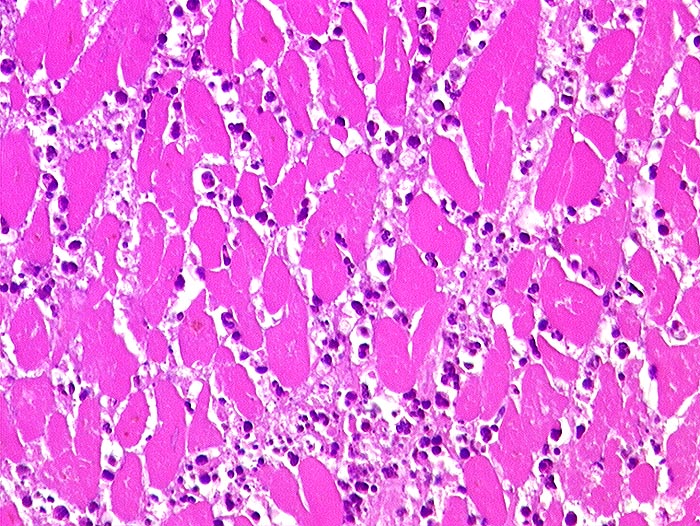

AP/ Akuter Myokardinfarkt

Akuter Myokardinfarkt

vaskulär / Durchblutungsstörung

Kardiovaskuläres System

Herz links

Pathologischer Befund

Normalbefund